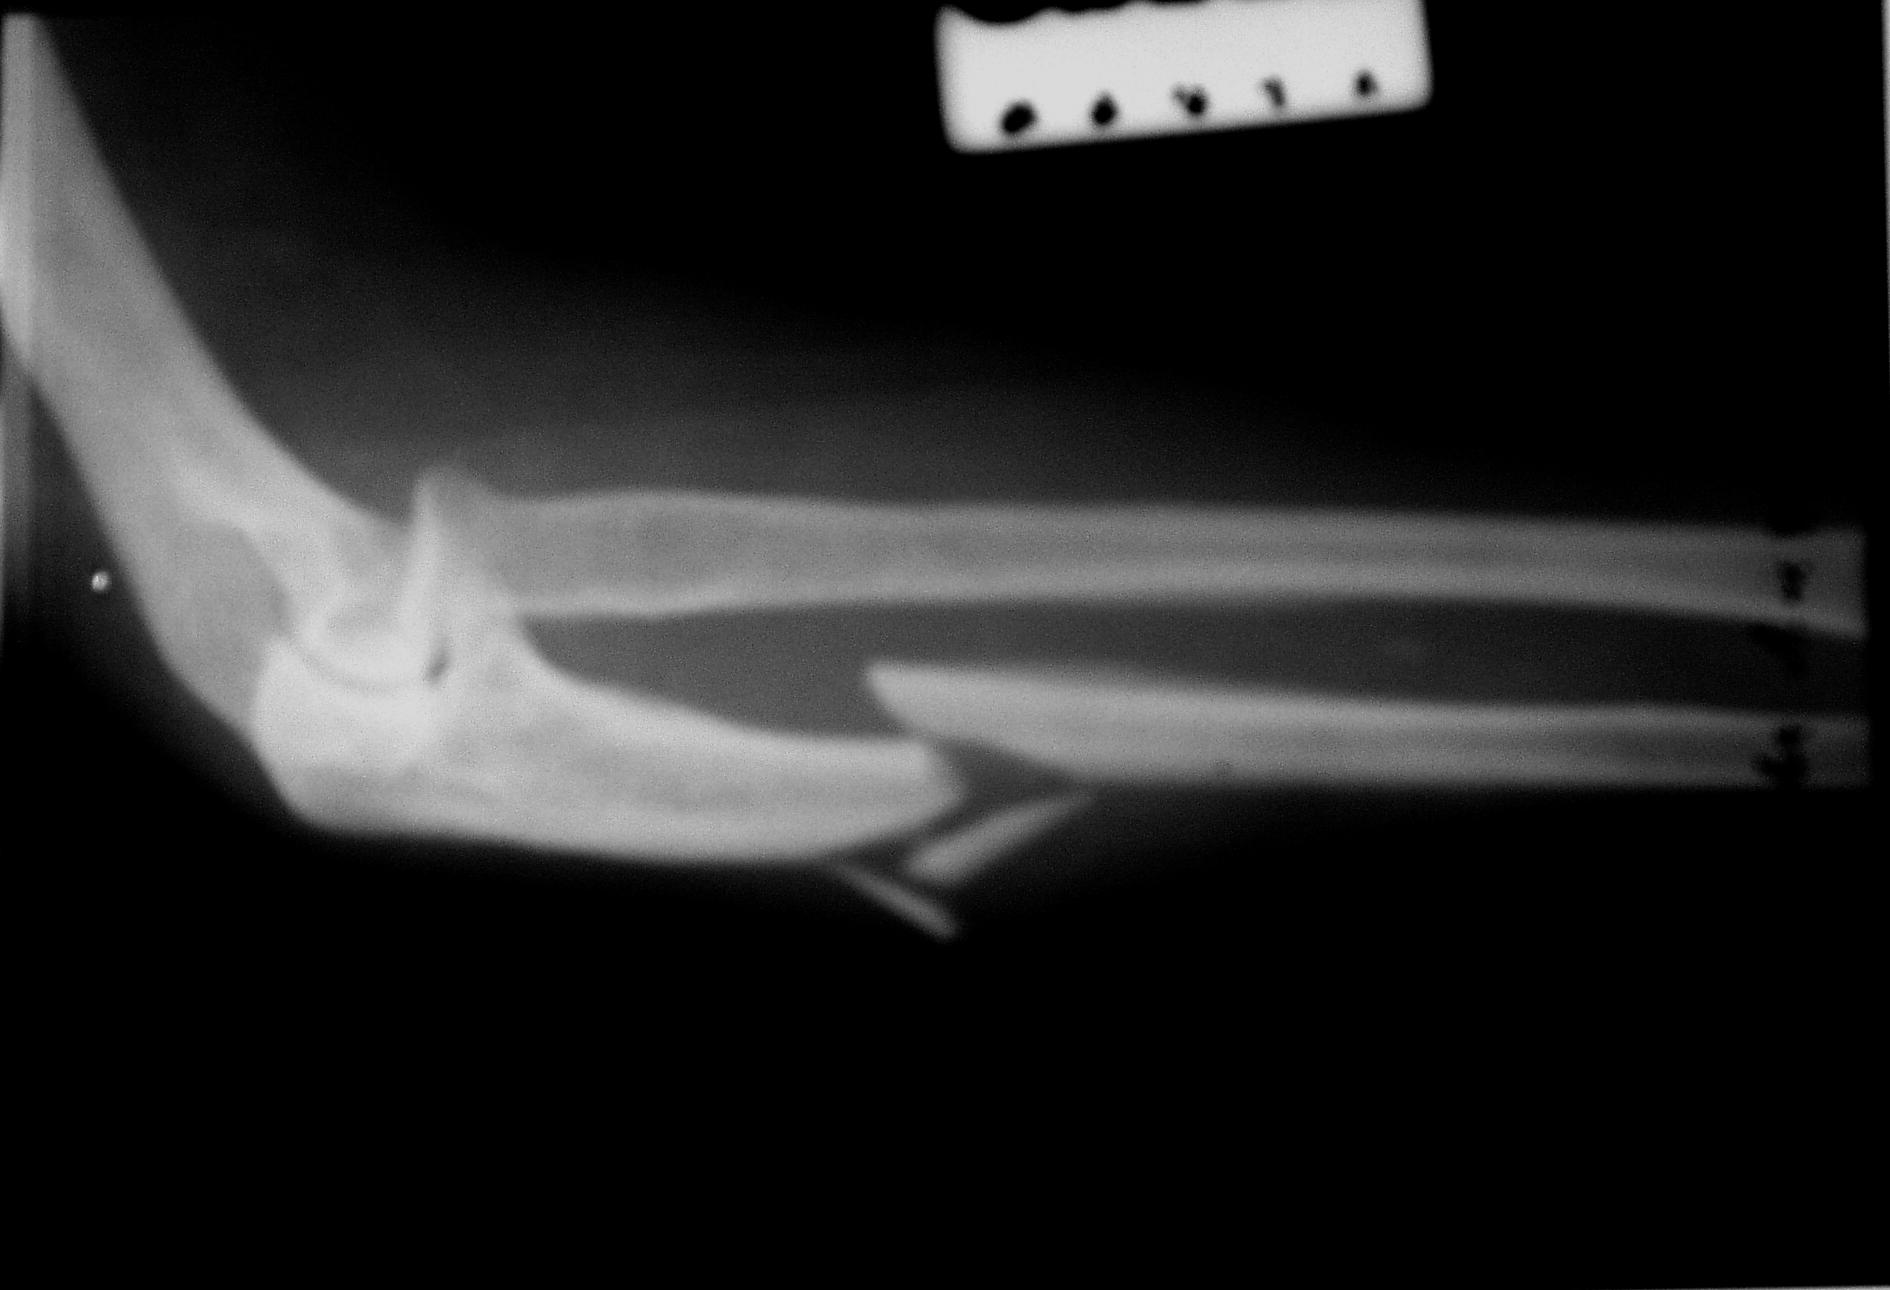

Изображения повреждения костей